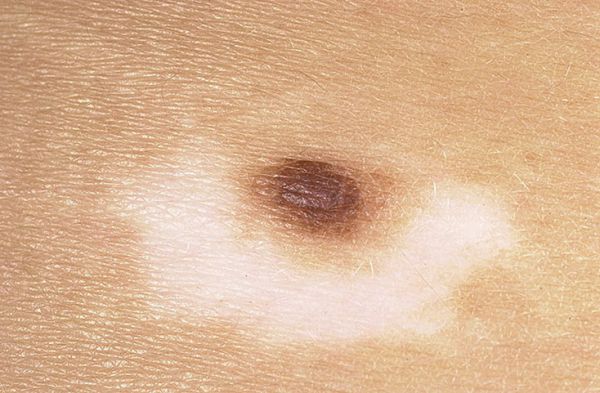

(от греческого слова «halos» — кольцо, круг). Он представляет собой образование, слегка возвышающееся над уровнем кожи, эластической консистенции, красновато-коричневого цвета, диаметром 2—5 мм, с характерной особенностью — наличием депигментированного венчика в окружности. Этот венчик в несколько раз больше пигментированного образования, располагающегося в центре. По мнению некоторых исследователей, галоневусы нередко сочетаются с иными неневоид-ными образованиями кожи, например с фиброэпителиальными невусами. Могут встречаться при раке внутренних органов.